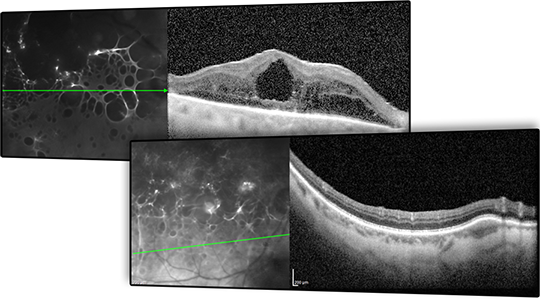

8.Módulo de Angiografia OCT

Imagem vascular não invasiva

O Módulo de Angiografia OCT SPECTRALIS® oferece imagens de OCTA de alta resolução, com uma resolução lateral de 5,7 μm/pix. Combinado com a precisão do TruTrack Active Eye Tracking, o módulo OCTA permite visualizar redes capilares finas com grande detalhe.

A resolução axial de 3,9 μm/pixel permite a segmentação de todos os quatro plexos vasculares da retina validados histologicamente. Lâminas personalizadas dentro dos plexos vasculares superficial e profundo oferecem uma avaliação clínica mais abrangente.

A ferramenta de remoção de artefatos de projeção (PAR) utiliza informações do plexo vascular superficial para remover artefatos das imagens OCTA. Isso possibilita uma visualização mais precisa da estrutura vascular e das patologias.